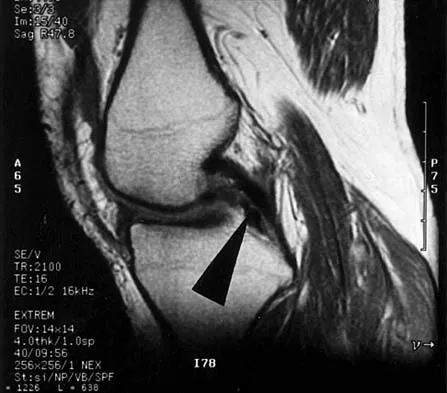

Figure 48 shows an MRI scan of the knee. The arrow is pointing to what structure?

Explanation